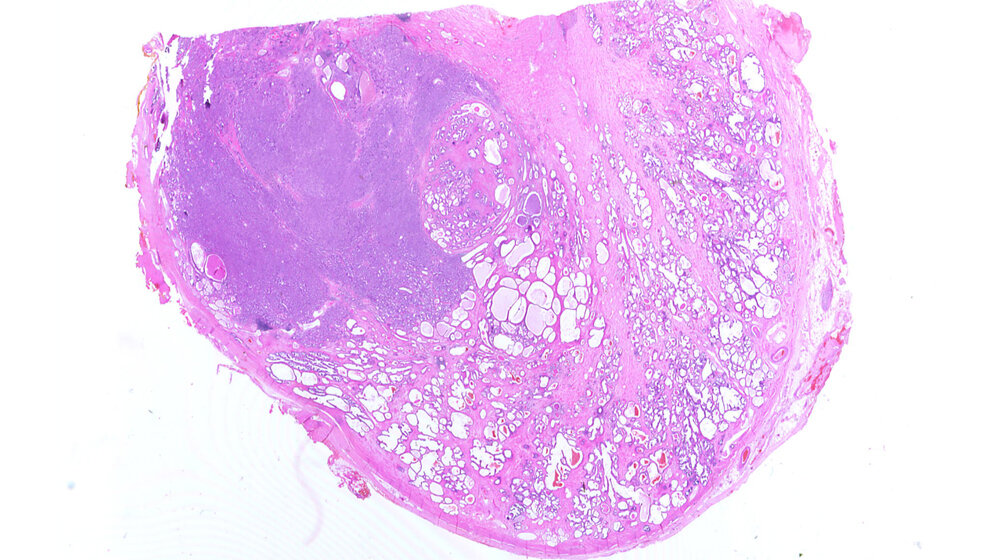

Das Prostatakarzinom ist in Deutschland gemessen an der Neuerkrankungsrate mit 23 Prozent aller Krebserkrankungen die häufigste Tumorerkrankung des Mannes. Jährlich sterben etwa 14.000 Männer an den Folgen von Prostatakrebs. Ziel des Screenings ist es, Prostatakarzinome mit einem hohen Progressionsrisiko in einem frühen Stadium zu entdecken, um den Krebs zu heilen. Derzeit kommen zwei Screening-Tests zum Einsatz: die digital-rektale Untersuchung und der Test auf das prostataspezifische Antigen (PSA). Die digital-rektale Untersuchung ist Teil des gesetzlichen Früherkennungsangebots für Männer ab dem 45. Lebensjahr, der PSA-Test nicht.